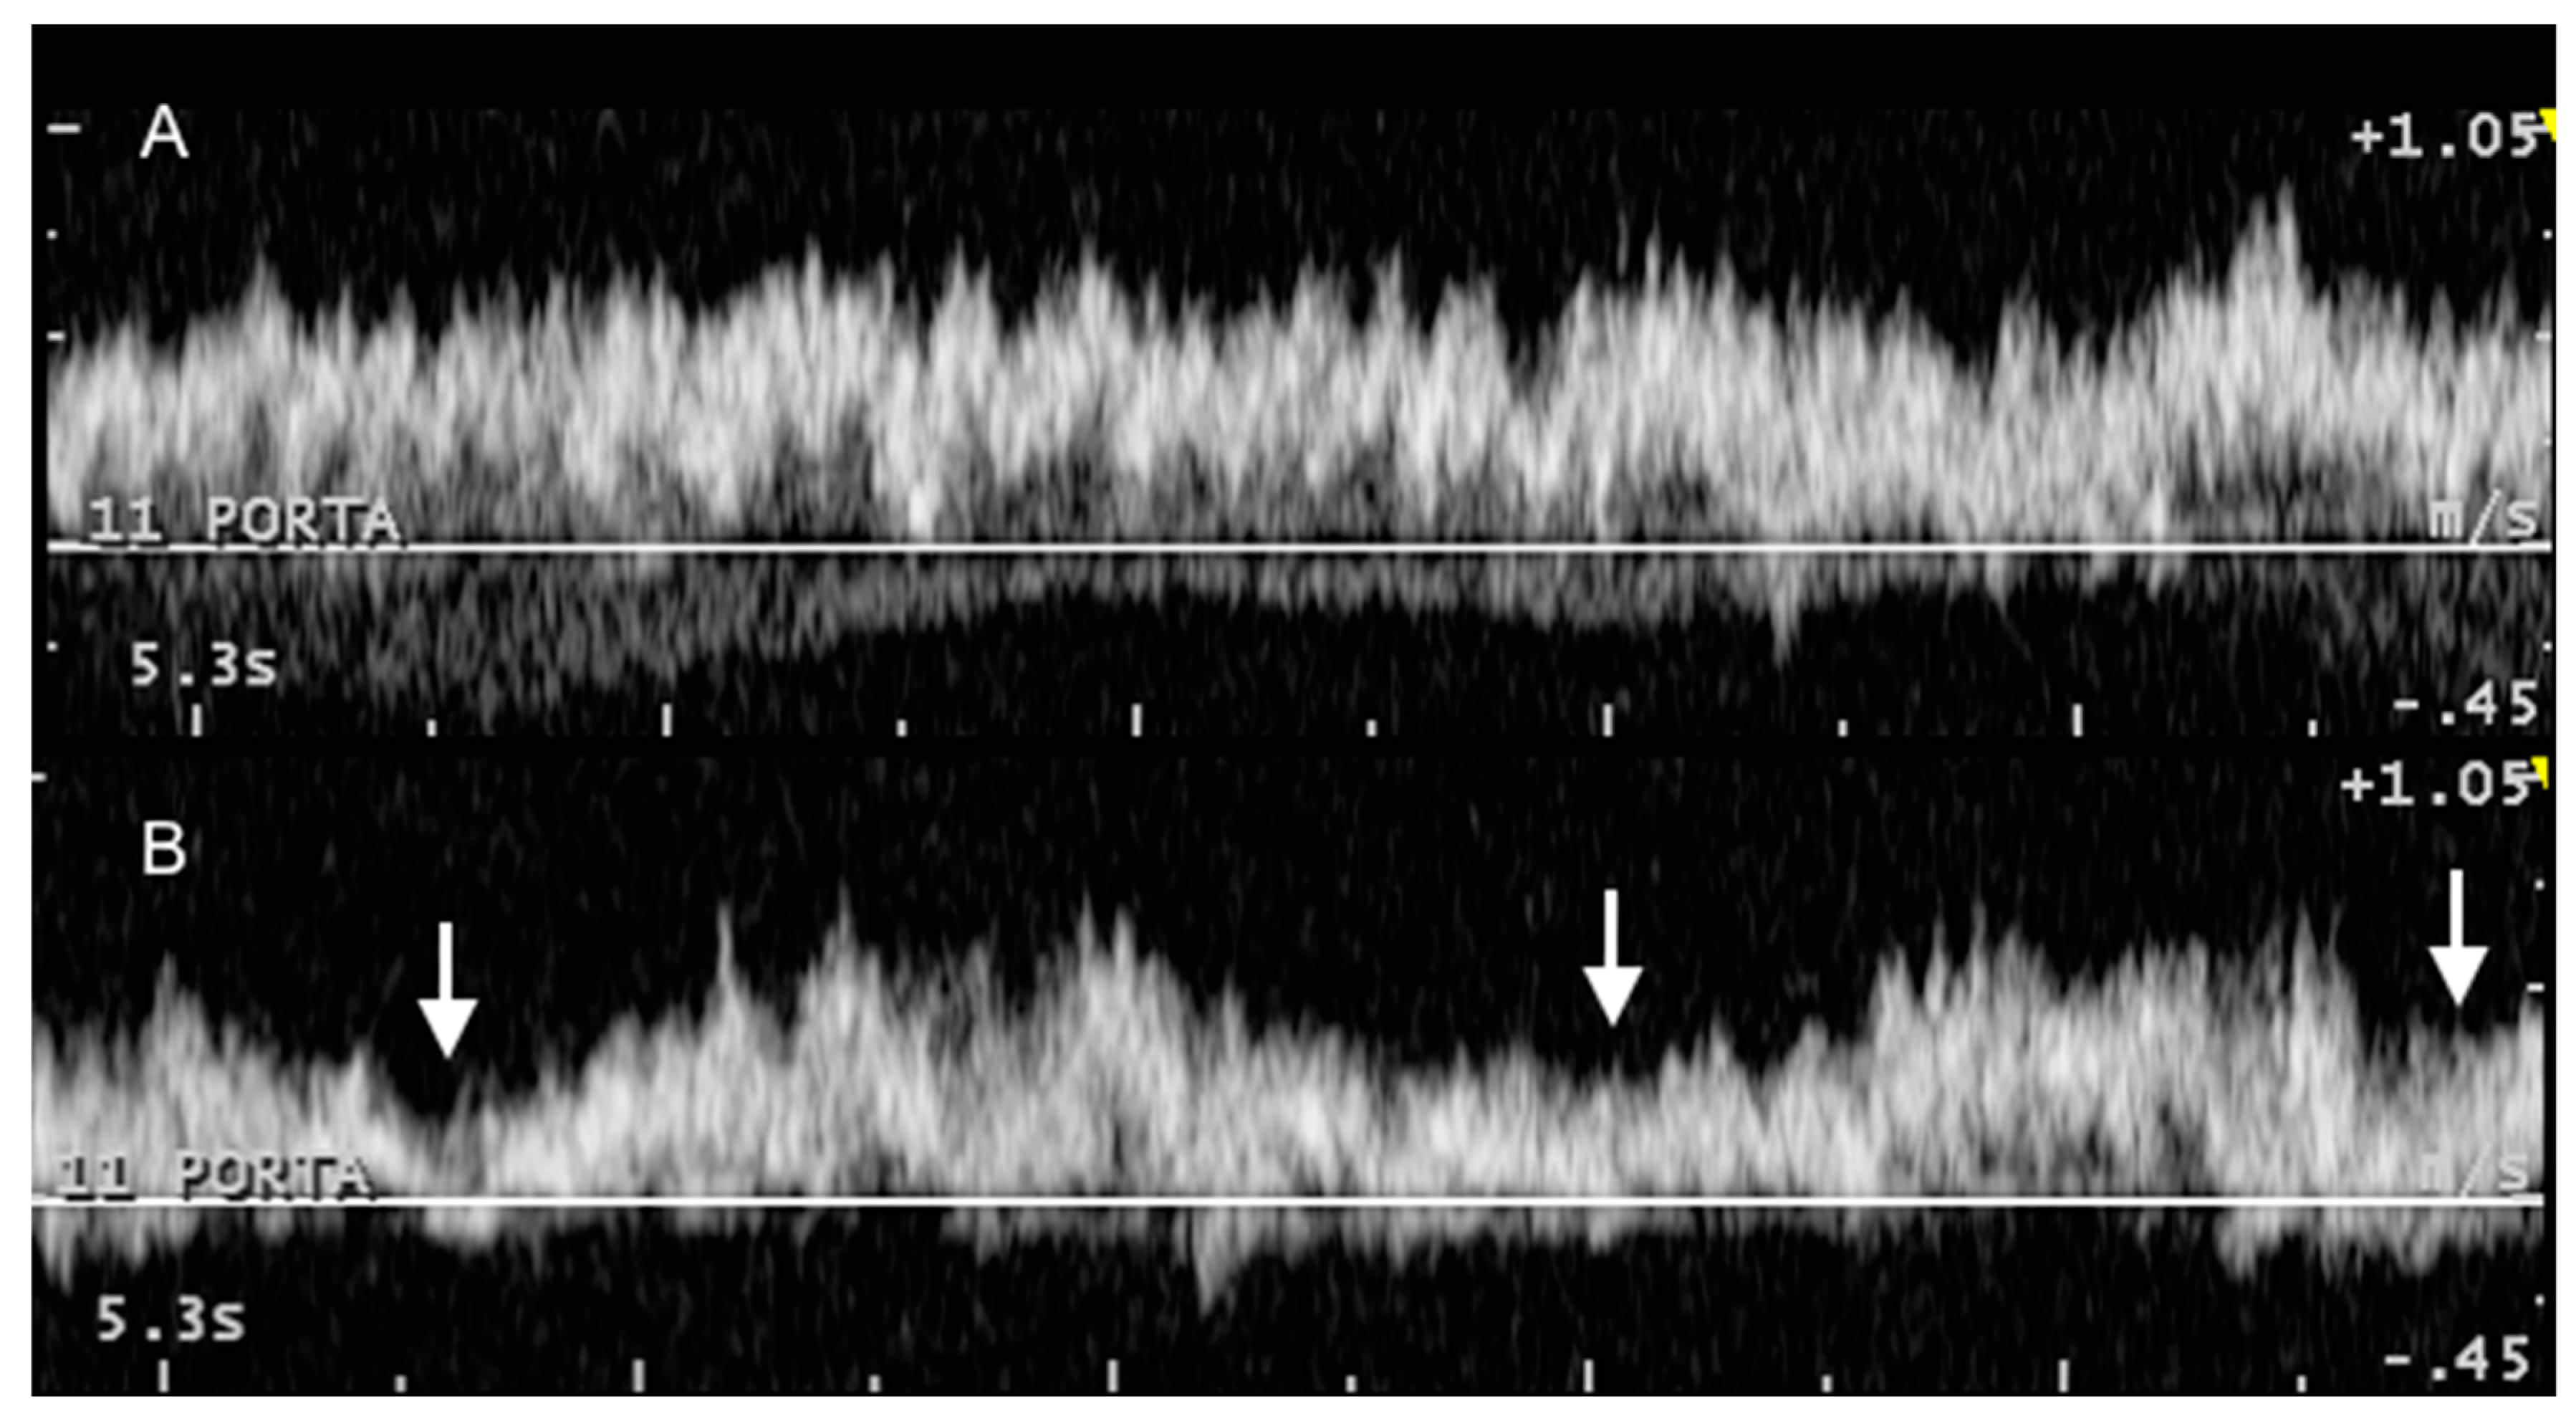

3.2. Portal System